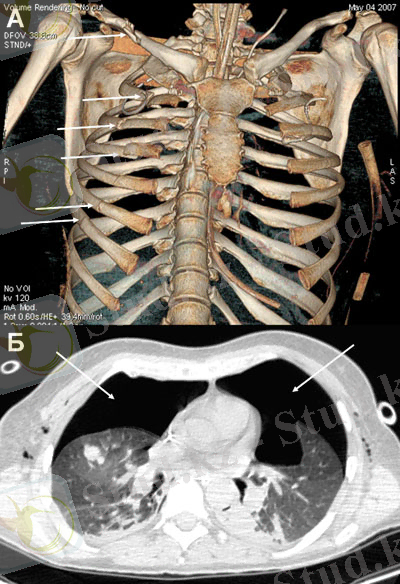

Қабырғаның сынуы

IV-YII қабырғалар жиі жарақаттанады. Жоғарғы қабырғалар

бұлшық еттерінің қалын болуымен, ал төменгі қабырғалар шеміршегінің эластикалық бөлігінің жақсы болуымен ерекшелінеді. Қабырға белгілі бір күштен иілуі, кеуде қуысының деформациялануы, сонымен қатар екі жағынан белгілі бір күш әсерінен сынуы мүмкін. Жарақаттың өте ауыр түрі қабырғалардың екі жерінен сынуы оны кеуде қуысындағы қабырғалардың екі жақты сынуы деп атайды. Бұл кезде тыныс алудың бұзылуынан оттегі жетіспеушілігі сонымен қатар плевропульмональды шокпен ерекшелінеді. Қабырғалардың сынуы плевраның, өкпенің қызметін бұзып пневмоторакс, гемоторокс немесе гемопневмотороксқа алып келеді. Жарақат алған науқастарда ауру терең дем алғанда, жөтелгенде күшейе түседі. Жарақаттанған адамда ісіну, көгеру сонымен қатар ентігу болады. Пальпация жасағанда бірден ауру сезімі сезіледі. Ауыскультация әдісімен өкпе қызметін (хрип, шум, трения превры), ал салыстырмалы перкуссия әдісімен плевра сұйықтығын (тимпанит, притупления) анықтайды.